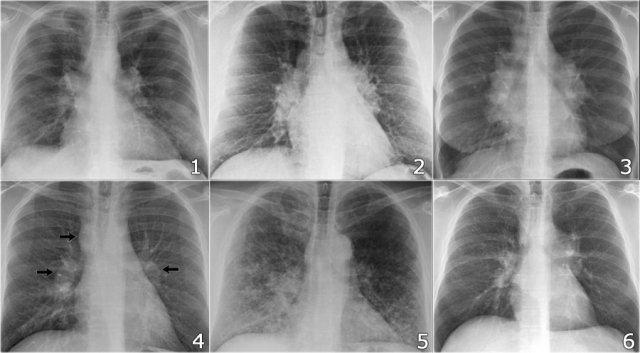

To rốn phổi – ca 1

Trong trường hợp này, bóng rốn phổi to ra ở cả hai bên. Nguyên nhân có thể do mạch máu giãn to hoặc hạch bạch huyết to. Một dấu hiệu rất có giá trị trong trường hợp này là khối nằm bên phải khí quản.

Đây được gọi là dấu hiệu 1-2-3 trong bệnh sarcoidosis, tức là to rốn phổi trái, rốn phổi phải và hạch cạnh khí quản.

Dưới đây là thêm một số ví dụ về bệnh sarcoidosis.

Nhấp vào hình để phóng to.

- Hạch bạch huyết to và hình ảnh kính mờ (ground-glass) ở phổi

- Hạch bạch huyết to, dấu hiệu 1-2-3

- Hạch bạch huyết to khối lớn

- Dấu hiệu 1-2-3

- Hình ảnh nốt ở phổi, không có hạch bạch huyết to

- Hạch bạch huyết rốn phổi và cạnh khí quản to